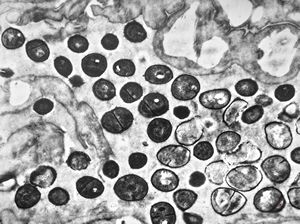

poxvirus - molluscum contagiosum